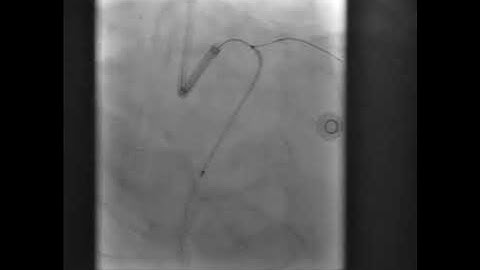

PCI of LCX CTO Using Antegrade Approach